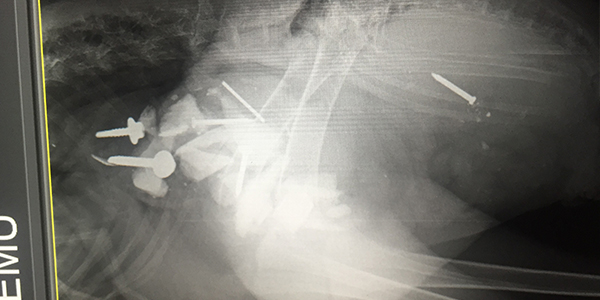

X-Ray of Emu showing foreign bodies ingested

Emergency surgery was performed on the Emu at RSPCA Queensland's Wildlife Hospital at Wacol, to remove metal objects from his stomach.

RSPCA Veterinarian Dr. Meghan Burrows performed the 2.5 hour surgery on “Digger” and says he’s extremely lucky.